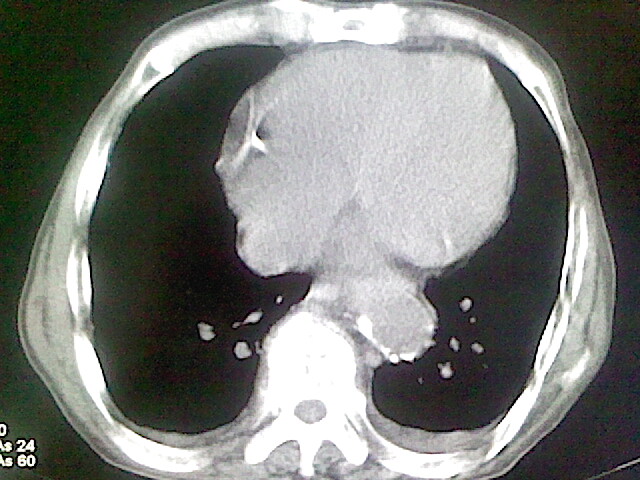

以下是引用zsl6918在2008-8-28 16:49:00的发言:[br]双肺炎性病灶,食管狭窄估计与心房增大压迫所致。

以下是引用xulianj在2008-8-28 20:36:00的发言:[br]慢支肺气肿伴感染,右上肺陈旧性结核;食道建议胃镜检查。

以下是引用wqs571018在2008-8-28 21:18:00的发言:[br]慢支继发感染,右上肺陈旧性结核;食道建议胃镜检查。